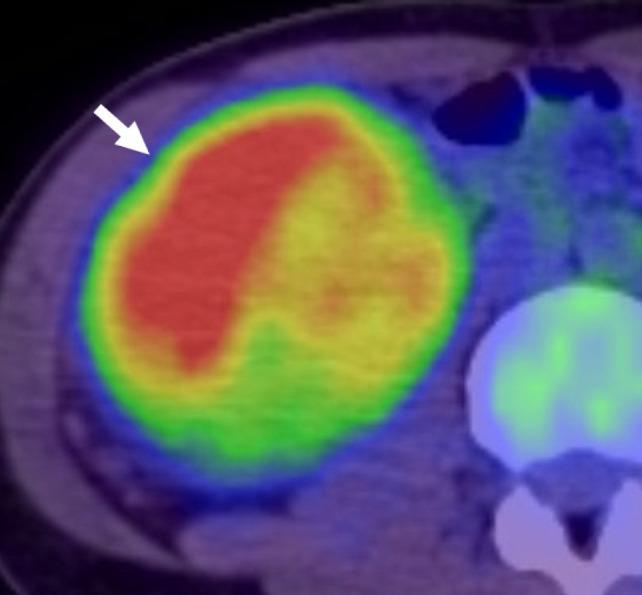

Translocation and transcription factor E3 (TFE3)-rearranged renal cell carcinoma (RCC) is a rare subtype of RCCs characterised by the fusion of the TFE3 transcription factor genes on chromosome Xp11.2 with one of the multiple genes. TFE3-rearranged RCC occurs mainly in children and adolescents, although middle-aged cases are also observed. As computed tomography (CT)/magnetic resonance imaging (MRI) findings of TFE3-rearranged RCC overlap with those of other RCCs, differential diagnosis is often challenging. In the present case reports, we highlighted the features of the fluorine-18-labelled fluorodeoxyglucose positron emission tomography with CT (FDG PET-CT) in TFE3-rearranged RCCs. Due to the rarity of the disease, FDG PET-CT features of TFE3-rearranged RCC have not yet been reported. In our cases, FDG PET-CT showed high standardised uptake values (SUVmax) of 7.14 and 6.25 for primary tumours. This might imply that TFE3-rearranged RCC has high malignant potential. This is conceivable when the molecular background of the disease is considered in terms of glucose metabolism. Our cases suggest that a high SUVmax of the primary tumour is a clinical characteristic of TFE3-rearranged RCCs.

易位性及转录因子E3(TFE3)重排的肾细胞癌(RCC)是肾细胞癌的一种罕见亚型,其特征为Xp11.2染色体上的TFE3转录因子基因与多个基因之一发生融合。TFE3重排的RCC主要发生于儿童和青少年,不过中年病例也有报道。由于TFE3重排的RCC的计算机断层扫描(CT)/磁共振成像(MRI)表现与其他RCC的表现重叠,鉴别诊断往往具有挑战性。在本病例报告中,我们着重介绍了氟-18标记的氟脱氧葡萄糖正电子发射断层扫描联合CT(FDG PET-CT)在TFE3重排的RCC中的特征。由于该疾病罕见,TFE3重排的RCC的FDG PET-CT特征尚未见报道。在我们的病例中,FDG PET-CT显示原发肿瘤的标准化摄取值(SUVmax)分别为7.14和6.25,较高。这可能意味着TFE3重排的RCC具有较高的恶性潜能。从葡萄糖代谢角度考虑该疾病的分子背景时,这是可以想象的。我们的病例提示,原发肿瘤的SUVmax较高是TFE3重排的RCC的临床特征。